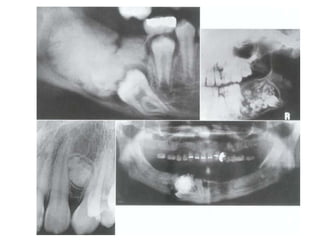

Cementoblastoma

( True Cementoma )

• Slow growing

neoplasm composed

of cementum.

• Usually solitary

lesion seen as a

growth on root of

tooth.

• Most common in

mandible, premolar

or 1st molar (80%).

24

• Appears as a well

defined RO area

with a thin RL band

around it

• May cause external

root resorption

25

• It not removed after

tooth extraction

• Remarks the RL

related to canine and

second premolar, it is

another

cementoblastoma in

the fibrous stage.

26

• Another case

remaining after tooth

extraction.

• It surrounded by the

radiographic signs of

chronic inflammation.

• Periapical cemental

dysplasia related to 4

tooth